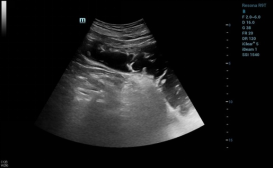

询问病史,患者口服雪碧7日,超声科张华斌主任特意嘱其改为饮用可乐。3日后患者腹痛症状较前明显好转,复查超声,胃结石神奇的消失了。

所见如下:

image.pngimage.png

5,6  胃腔内未见结石